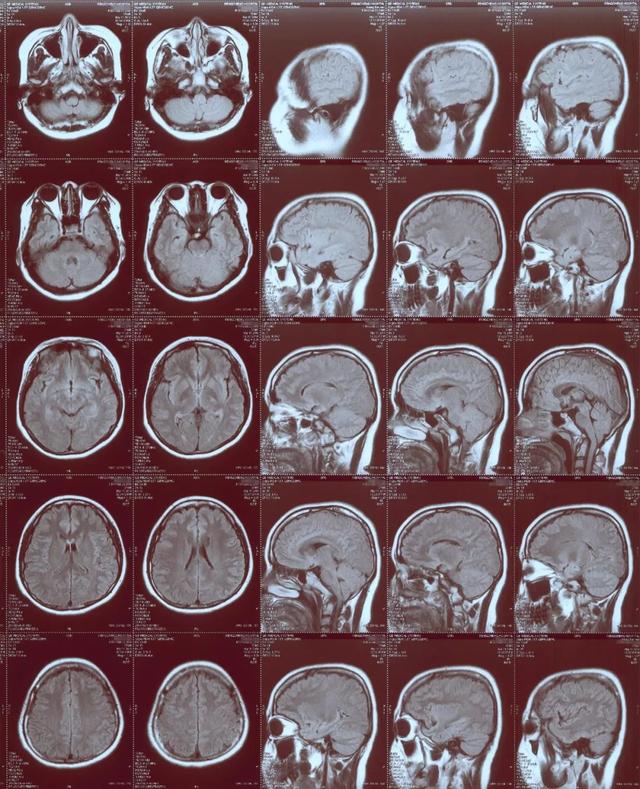

空洞症

嵴髓空洞症(空洞形成,胶质增生)_财富号_东方财富网

图片尺寸555x439